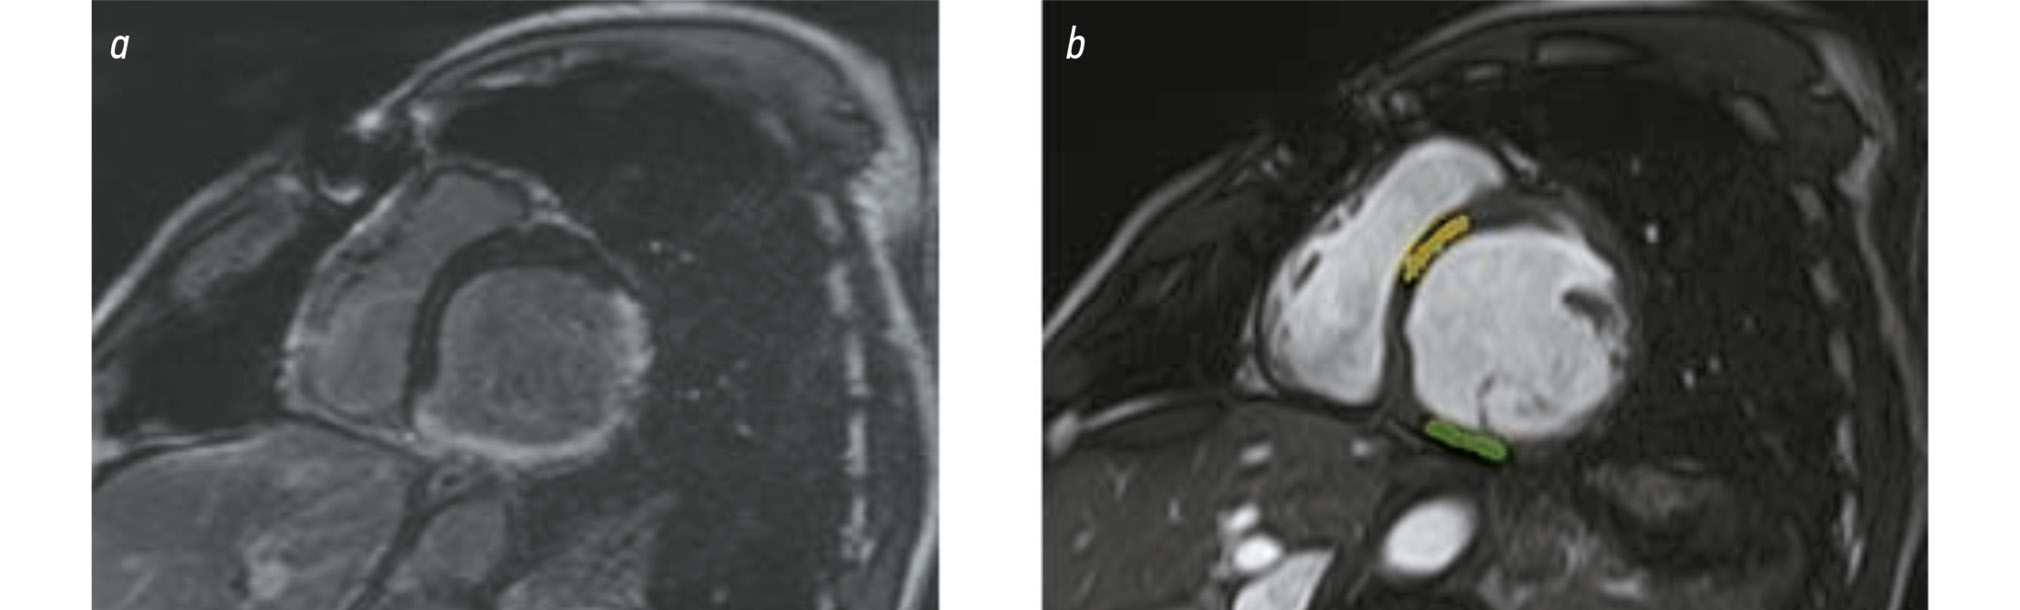

Regions of interest (ROIs) were manually selected to assess differences in radiomic features between intact myocardium and PICS areas. The size and position of the ROIs corresponded to the PICS areas and intact myocardium regions based on time-delayed contrast-enhanced MRI images. Initially, ROIs were manually selected on MRI slices along the short axis (in SSFP mode) that matched the PICS areas on post-contrast MRI images. Texture features were then extracted using the PyRadiomics library. The ROI selection process is illustrated in Fig. 1.

Fig. 1. Selection of regions of interest in post-contrast and non-contrast-enhanced cardiac MRI images, short axis view. a: time-delayed contrast-enhanced MRI showing transmural contrast uptake along the LV inferior wall with no signs of damage in the interventricular septum. b: cardiac cine-MRI showing regions of interest in the posterior wall (green), corresponding to a PICS area in the inferior segment at the middle LV level, and in the anteroseptal segment at the middle level (yellow), corresponding to an intact interventricular septum.